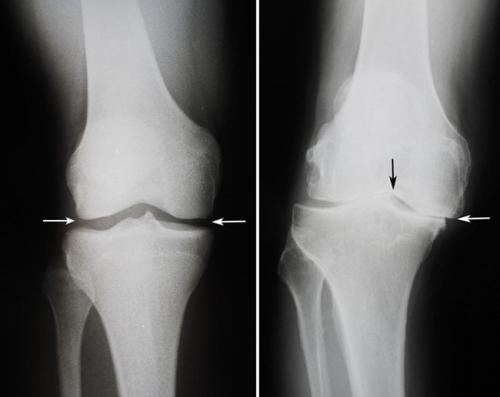

- дегенеративно-дистрофические. Чаще встречаются у пожилых людей и лиц, которые постоянно выполняют тяжелую физическую работу. Дегенеративные процессыэто следствие старения организма, которое сопровождается замедлением метаболизма и кровообращения в суставах. Под действием провоцирующих факторов (физические нагрузки, нехватка кальция, обменные нарушения) суставные хрящи начинают разрушаться, что приводит к развитию патологии. Дегенеративно-дистрофические заболевания имеют хроническое, медленно прогрессирующее течение;

Большеберцовая кость расположена на голени медиально (с внутренней стороны) и, как и бедренная кость, имеет два мыщелка: латеральный и медиальный, а между ними небольшое поднятие – межмыщелковое возвышение. Поверхность мыщелков большеберцовой кости практически плоская, лишь с небольшой вогнутостью, тогда как мыщелки бедренной кости заметно более выпуклые. Из-за этого возникает небольшое несоответствие суставных поверхностей, которое корректируется наличием особых хрящевых прокладок – менисков. Их в коленном суставе также два: латеральный и медиальный. Верхние их поверхности соответствуют по форме мыщелкам бедренной кости, а нижние – мыщелкам большеберцовой кости.